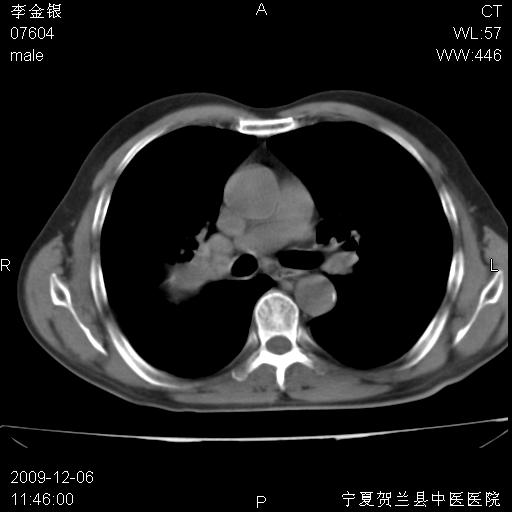

该病人 ,男,62岁,主因咳痰带血两天

考虑右肺中央型占位性病变并阻塞性肺炎.(右肺上叶支气管变窄),建议支纤镜检查.

考虑右肺中心型肺癌伴阻塞性肺炎及右肺门淋巴结转移,建议纤维支气管镜进一步检查。

支气管壁明显增厚 管腔狭窄,腔静脉后多个淋巴肿大,结合年龄病史考虑右肺上叶中央型肺癌并阻塞性肺炎

右肺上叶后段支气管阻塞,右上肺门占位,相应肺段阻塞性肺炎,右肺门有淋巴结肿大。诊断右肺上叶中心型肺癌,阻塞性肺肺炎、右肺门淋巴结转移。

符合中央型肺癌的ct表现并肺出血。但有一点腔静脉后有一钙化的淋巴结啊

右上叶支气管狭窄,管壁增厚,远端斑片状软组织影,病灶邻近叶间裂,叶间裂无移位。

诊断右肺中央型肺癌。

那个片影应该大部分都是病灶,病灶沿肺段支气管分支生长,后段完全显示不清、闭塞。若为不张应该伴有叶裂的移位,若为炎症应有空气支气管征。

右肺中心型肺癌伴阻塞性肺炎及右肺门与纵膈淋巴结转移很典型,可纤维支气管镜进一步检查

考虑右侧中央型肺癌伴右肺上叶后段阻塞性炎症、肺不张、右肺门和纵隔淋巴结肿大。

右肺上叶中心型肺癌,阻塞性肺炎、右肺门和纵隔淋巴结转移。